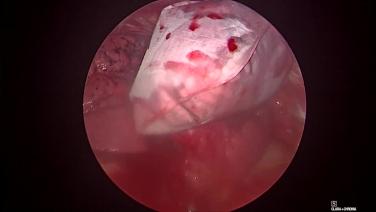

Thorascopic Lobectomy - Remove the Specimen